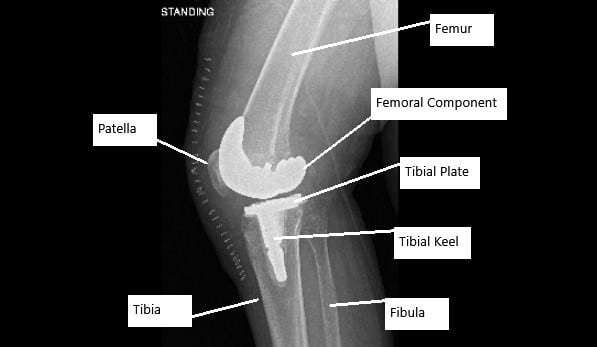

X-ray showing total knee replacement surgery in a patient with AVN knee.

- Total Knee Replacement: In severe cases, when the joint is extensively damaged, knee replacement surgery may be required. This procedure involves removing the damaged bone and cartilage and replacing them with artificial components.